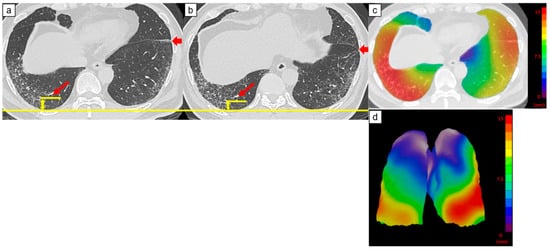

2.3.1. Architectural Distortion Measurement by 3D-AD